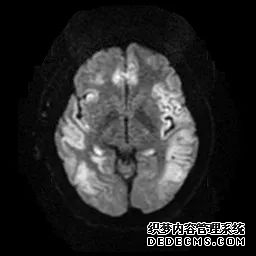

脑MRI显示尾状核、扁豆状核和脑梗头部T2/FLAIR呈双侧对称异常高信号。扩散限制涉及这些区域,其特征是扩散加权DWI(B-1000)上的高强度,ADC图上相应的减弱强度。

低血糖性脑病是一种代谢性脑病,它是由脑细胞对葡萄糖的供应和使用之间的不平衡引起的。脑MRI,尤其是DWI是诊断和预测该病预后的重要工具。

这个病例说明了低血糖脑病,有典型的病史和血液指标,结合MRI表现,DWI为诊断提供了最好的线索。

影像影响内囊后肢、大脑皮层(特别是枕叶和岛叶)、海马和基底节区,常是双边对称性的。